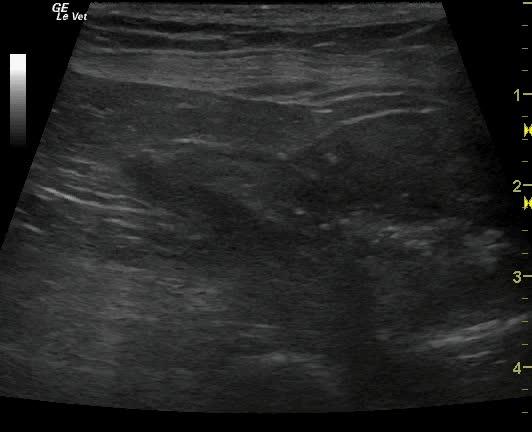

A 15-year-old NM West Highland White terrier dog was presented for evaluation of polydipsia, polyuria and possible bladder stones noted on radiographs. Abnormalities on CBC and serum biochemistry were thrombocytosis, neutrophilia, and hyperalbuminemia. Urinalysis was not performed owing to financial constraints however an abdominal ultrasound prescription was approved.